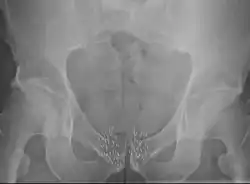

Cancer de la prostate

La curiethérapie pour traiter le cancer de la prostate peut être appliquée soit par l'implantation permanente de grains BDD soit par curiethérapie HDD temporaire[19],[59],[60]. L'implantation permanente des grains est adaptée aux patients qui ont une tumeur localisée et de bon pronostics de guérison[8],[59],[61],[62]. Il a été démontré que c'est un traitement très efficace contre la récidive[6],[8]. La taux de survie est similaire à celui observé avec la radiothérapie externe ou la chirurgie (prostatectomie radicale), mais avec moins d'effets secondaires tels que l'impuissance et l'incontinence[14]. La procédure peut être réalisée rapidement. Les patients sont généralement en mesure de rentrer chez eux le jour même du traitement et de retourner à leurs activités normales après 1 à 2 jours[3]. L'implantation permanente de grains est souvent une option moins invasive du traitement par rapport à l'ablation chirurgicale de la prostate[3].

La curiethérapie temporaire HDD est une approche nouvelle pour traiter le cancer de la prostate, mais reste moins fréquemment utilisée, moins fréquente que l'implantation permanente de grains. Cette technique (également appelée boost thérapie) est employée de manière à offrir une dose supplémentaire par rapport à la radiothérapie externe. En effet, elle offre une méthode alternative pour délivrer une dose élevée de radiothérapie adaptée au type de tumeur de la prostate, tout en épargnant les tissus environnants de l'exposition aux rayonnements[9],[10],[60],[61],[11],[63]. La curiethérapie HDD comme amélioration pour le traitement du cancer de la prostate signifie aussi que les séances de radiothérapie externe peuvent être plus courtes que quand la radiothérapie externe est utilisé seule[9],[10],[63],[64].